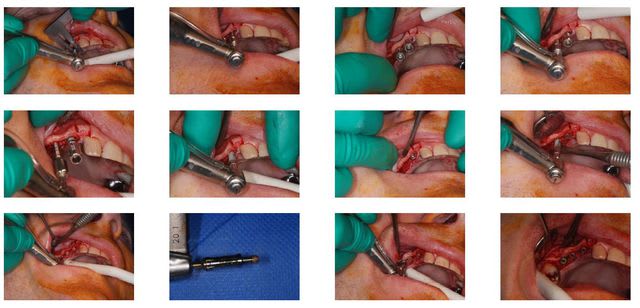

Ben voilà! c'est fait!

Alors pour résumer j'ai fini par me lancer sur ce cas en 17 et 16 j'ai pu poser un 4*9 et un 4*8 avce l'aide des ostéotomes.

En 12 un 3,5*11 après extraction et curetage de l'alvéole.

Enfin pour ce qui est de l'expansion, merci à pxav de m'avoir fait découvrir messinger... c'est vraiment magique, même si faut pas être préssé!

saignée de 16 à 13 au disque puis àn la fraise flamme et puis passage des spreaders doucement au moteur et pour satisfaire ma curiosité j'ai aussi pu essayer les distracteurs.

J'ai eu une petite fracture de crete de 2-3 mm en 15 du coup j'ai pas osé poser sur ce site, par contre en 14 et 13 pose de 3,5*9

Au niveau du comblement osseux, j'ai eu un peu peur de mettre du vitalos que je ne connais pas du tout j'ai donc mis du biobank.

Pour l'autocritique pas mal de choses:

-la longueur des implants, j'ai pas osé mettre des 11 j'ai eu peur de tout casser en étant trop gourmand, j'ai apres coup des regrets en 16 et 17 (au point ou j'en étais j'aurais pu faire un Summers)

- la petite fracture Même si j'avais pas mal buché, j'avoue que je savais pas trop quoi faire ( pose quand même et greffe??, ROG?? enlever le fragment/le conserver??)

- la lenteur: 3 heures 40 pour 5 implants j'aivais jamais été aussi lent...

Reste plus qu'à voire si tout ça prend... Merci à tous pour les conseils et plus particulièrement à pxav pour avoir pris le temps de répondre à toutes mes questions et même d'avoir fait l'étude de scan!!